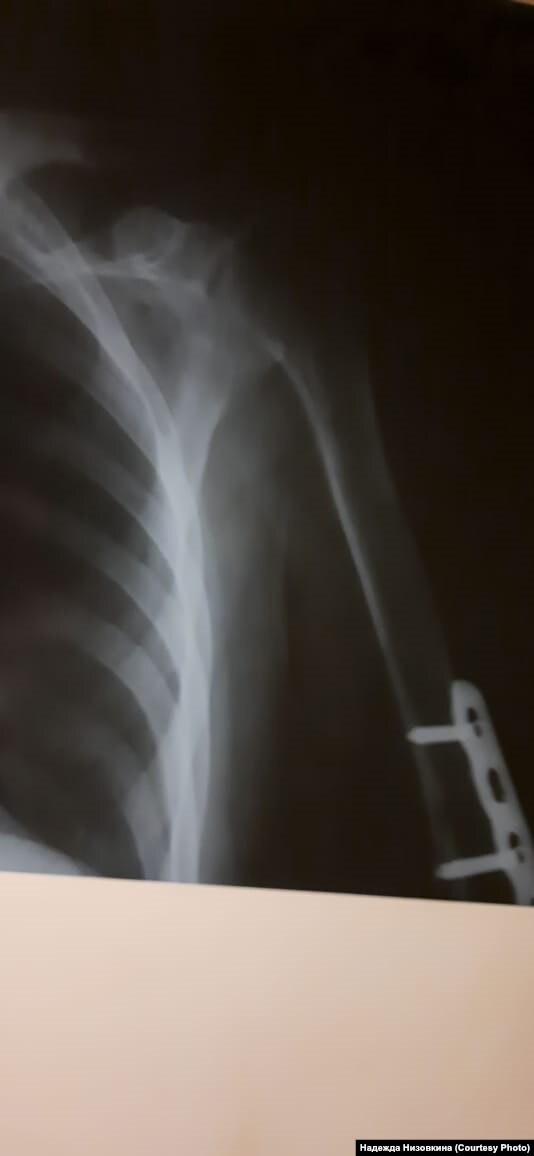

– Меня долгое время не пускали не то что в Советский отдел полиции, а даже во двор, все перекрыли! – возмущается адвокат Баирова Надежда Низовкина. – Подобное "задержание" и сокрытие человека – это, безусловно, преступление. Дмитрию же при этом еще и повредили руку – когда скрутили, задели штыри в руке, установленные после перелома, сейчас его мучают сильные боли. Потому что, найдя его через прокурора(!), мы добились, что его осмотрели медики, сделали снимки (медосвидетельствование показало повреждение мышечной ткани на месте сросшегося перелома), поставили обезболивающее, но продолжат ли его ставить – большой вопрос.

Рентген сломанной руки Дмитрия Баирова, Улан-Удэ, 28 января

Опасения у адвоката вызывает и тот факт, что, несмотря на серьезность диагноза, на последней странице медзаключения (есть в распоряжении редакции) стоит отметка "содержание в ИВС не противопоказано".